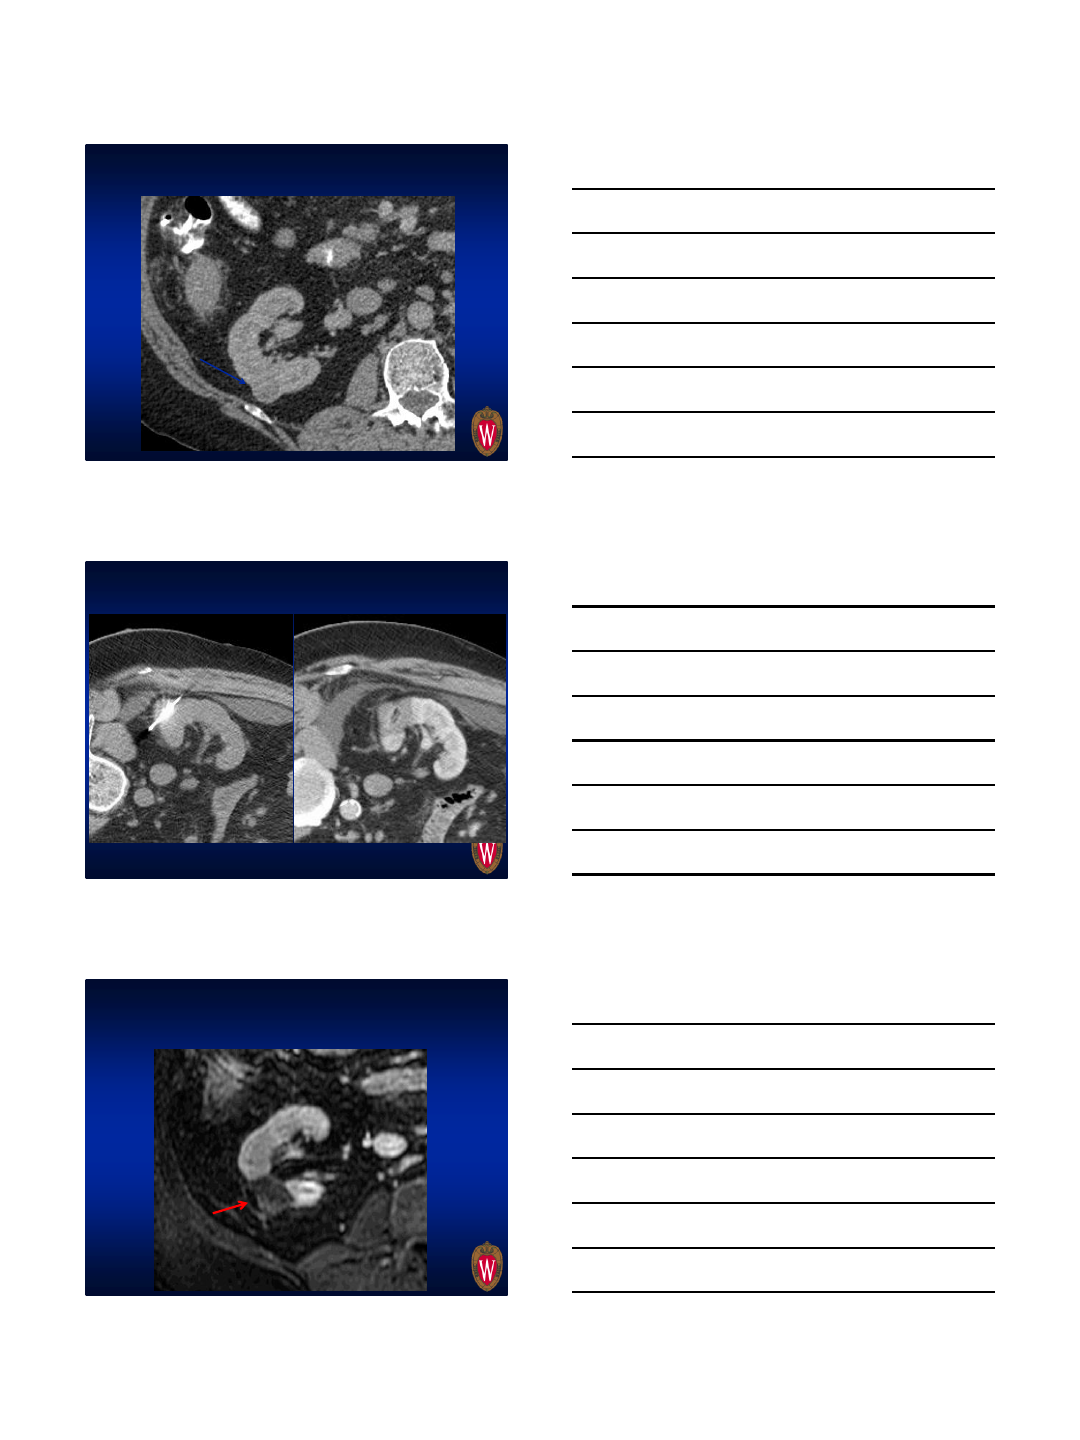

Tangential approach to avoid collecting

system

2.9 cm

Immediate Pre Immediate Post ablation

7 months post ablation